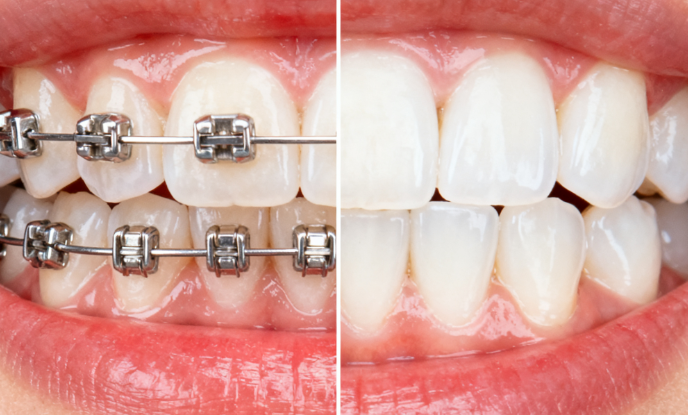

总之,SGTB矫正器每天戴几个小时对于矫正疗效至关重要。了解不同情况下的佩戴要求、掌握正确的佩戴方法和注意事项,以及清楚整个治疗周期,能够帮助你更好地进行牙齿矫正。不过,具体佩戴时间和治疗方案应严格遵循主治医师的个性化建议,并定期复诊检查矫正进度。希望大家都能通过正确佩戴SGTB矫正器,拥有整齐美观的牙齿。